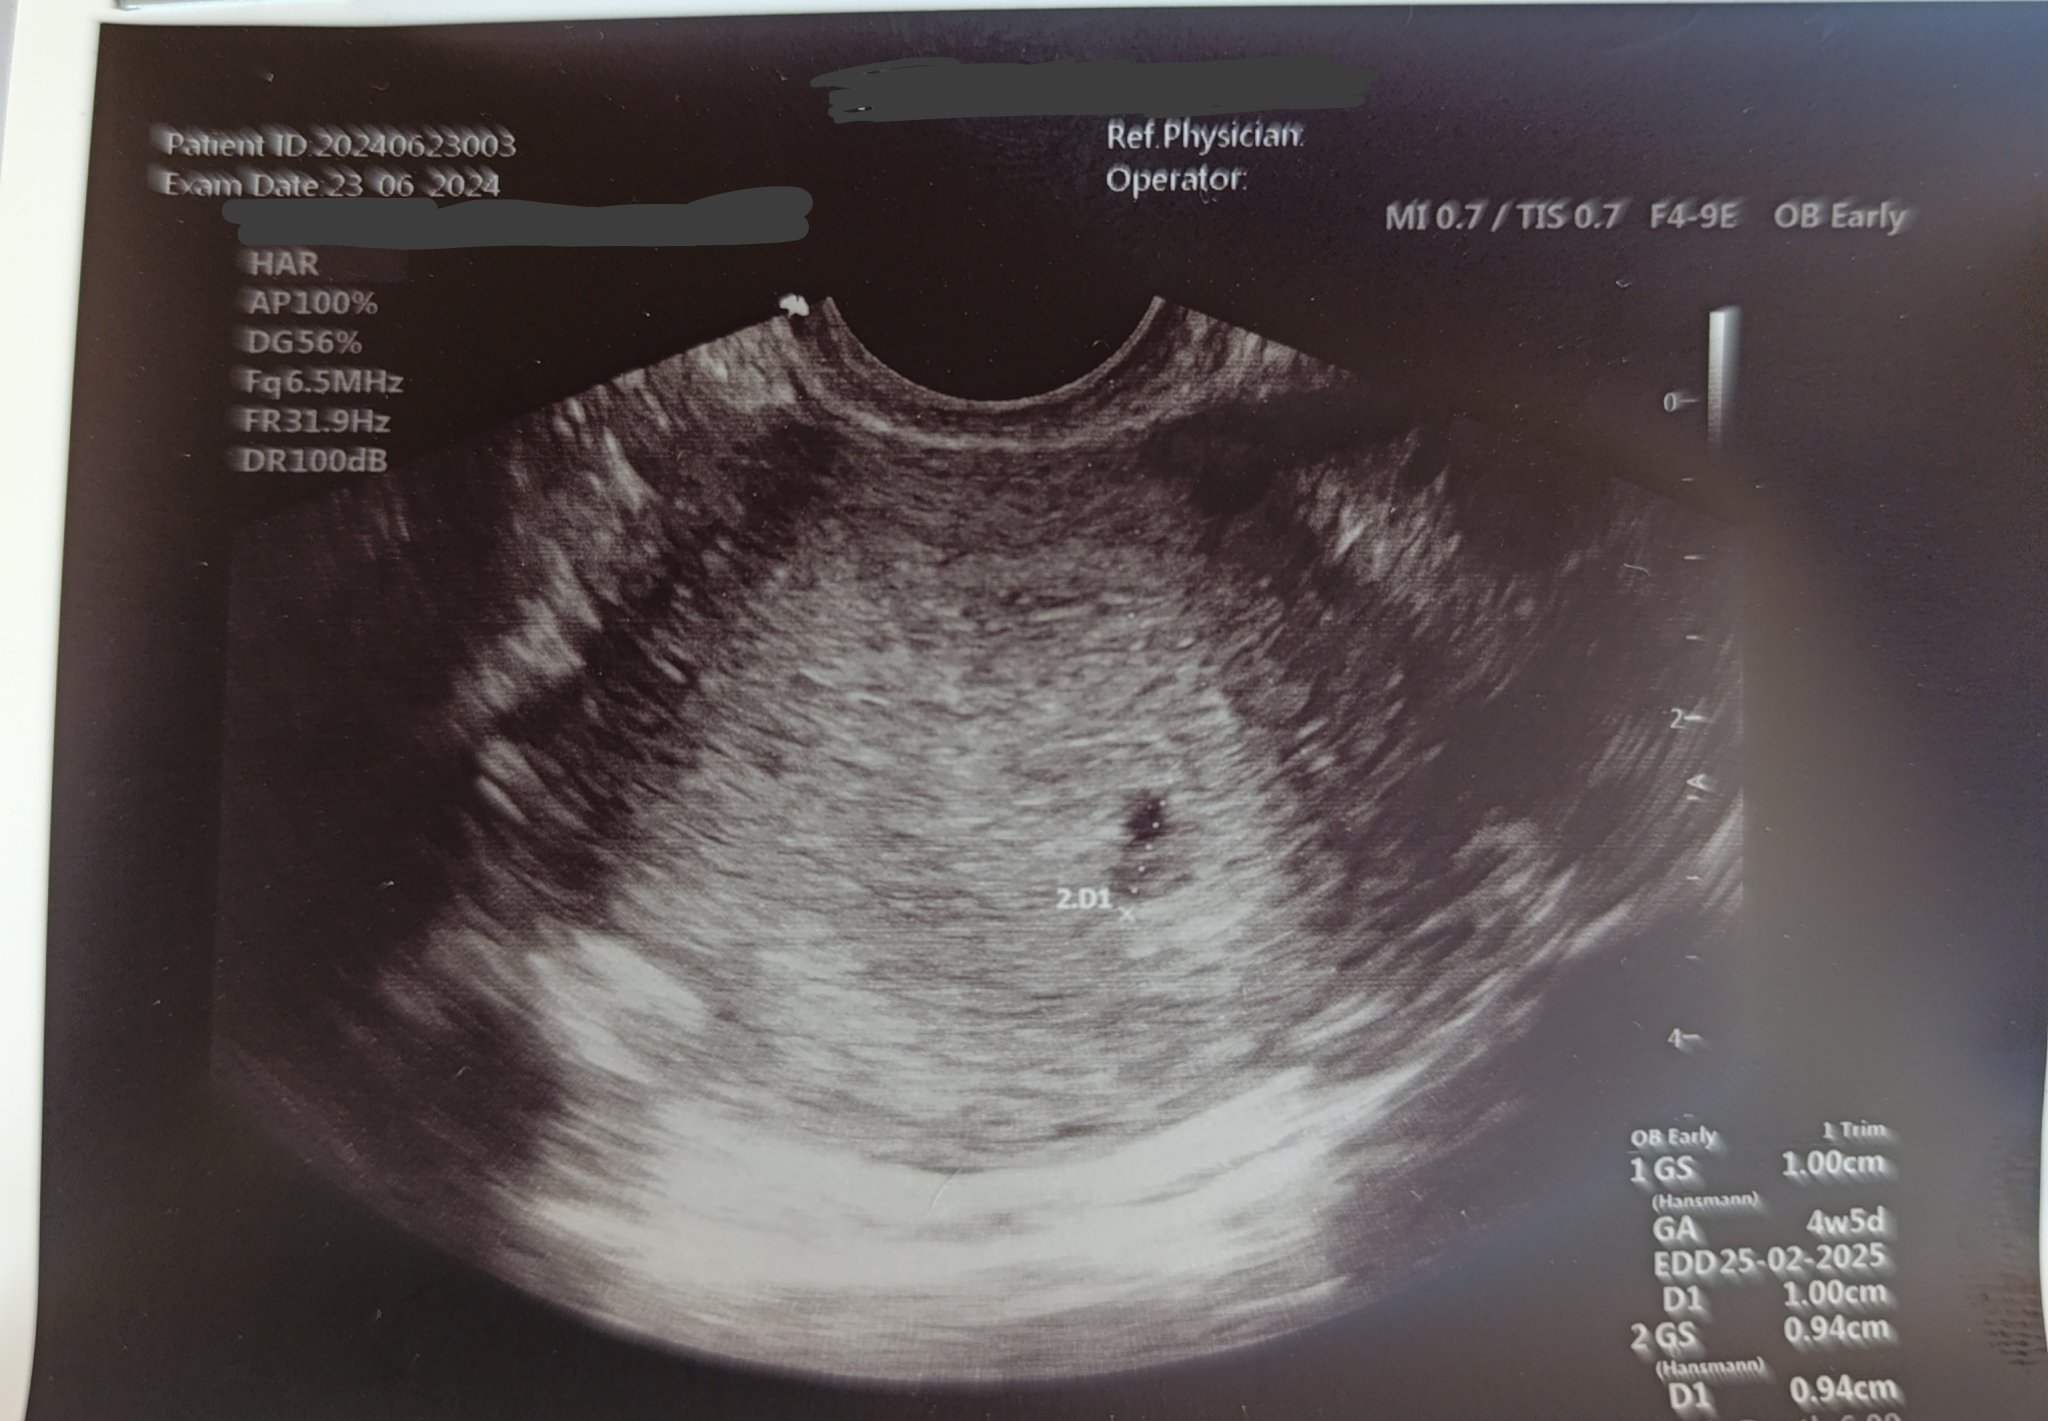

Искам вашето мнение дами. Месец след спонтанен аборт забременях отново, направих 3 изследвания ЧХГ като се удвояваха нормално. Вчера бях на преглед (в 4та седмица съм) и доктора ми каза, че плодния сак бил прекалено малък и не отговарял на седмицата, каза, че според него плода няма да се развие. Има ли някоя дама с подобен случай и колко мм или см ви е бил плода? Ще ви покажа и снимка за мнение. Благодаря предварително! Утре отново ще пусна ЧХГ да видя дали се удвояват нормално, последното го правих на 17ти.

Здравей. Не съм специалист, но това 1 см е 1мм всъщност. Има два гестационни сака. В началото по тях се определя гестационната възраст.

Относно ехографската снимка не е и нужно да си лекар, за да я разчетеш. Пише, че плода е 1см и отговаря на 4та седмица и 5дни. Последния ми месечен цикъл е на 6ти миналия месец.

1. 4+5 е 5г.с.

2. Абсурд да се види плод 1 см в тази седмица.

В 5 г.с. само се установява дали ембрионът е в матката или развитието е неправилно (тръба). ЧХГ трябва да ви е сега над 1000. В 6-та вече може да чуете сърчицето. Изчакайте 10 дни и отидете да му чуете сърчицето.